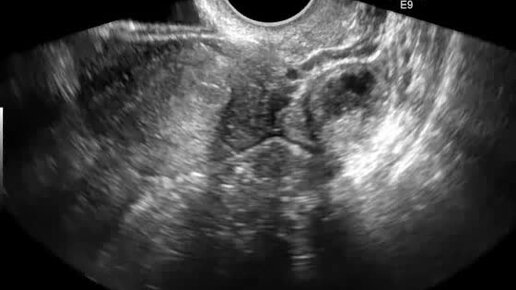

Другая пациентка. Поперечное сканирование матки. Левый яичник у угла матки. Спаечный процесс